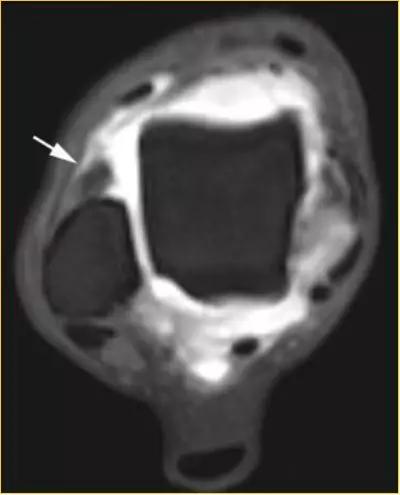

5.后内侧撞击综合症:

影像学表现为距骨胫骨间肌腱及趾长屈肌腱水肿、增厚,内踝及距骨后内侧骨赘形成。

轴位示意图示后内侧撞击综合征:M:内踝;L:外踝;TP:胫后肌腱;FDL:趾长屈肌腱;Talus:距骨。短箭:距骨胫骨间肌腱深层纤维;箭头:距骨胫骨间肌腱后部纤维。

X线平片示胫骨后部骨赘形成,MR质子像黑箭示胫骨内后侧骨赘形成,白箭示内后侧软组织增厚, 白箭头:胫后肌腱;黑箭头:趾长屈肌腱